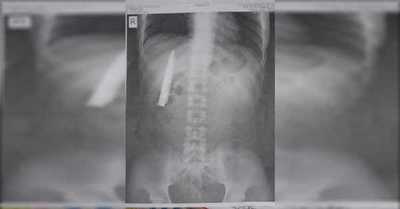

Hombre descubre una hoja de cuchillo dentro de su torso un año después de ser apuñalado - SNT

"Siempre me pregunté por qué siento algo de dolor en mi pecho cuando el clima es frío", dice Kent Ryan Tomao. [Leer más]

Hombre descubre una hoja de cuchillo dentro de su torso un año después de ser apuñalado - C9N